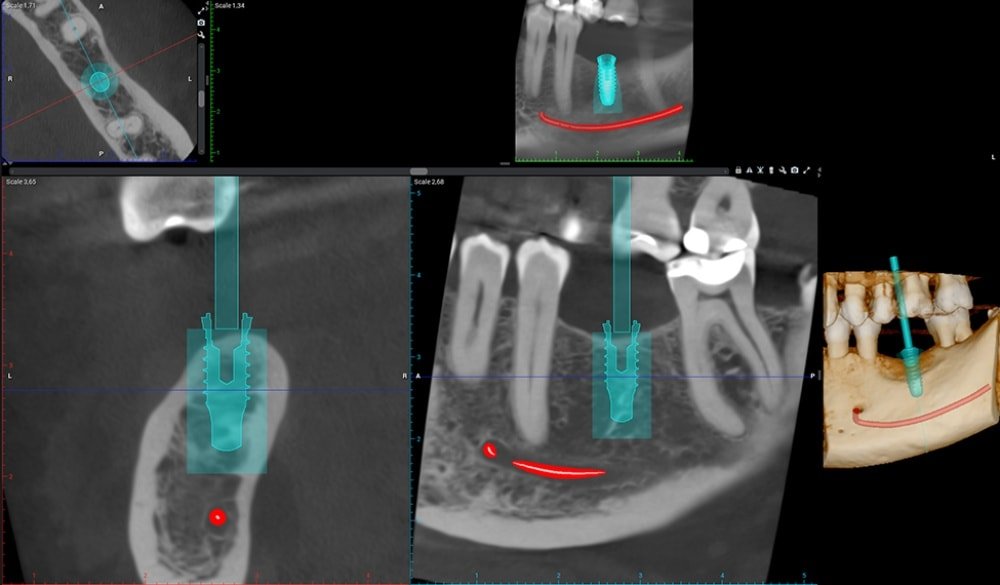

CONEBEAM ou (Scanner)

Le cabinet est équipé d’un appareil de radiographie haute technologie :

un tomographe volumétrique numérique, connu également sous le nom de scanner 3D.

Dans le cas d’un bilan pré-implantaire ou dans le cas de recherche de foyers infectieux, un bilan radiographique 3D est indispensable au docteur Alexandre ORLICK

En une seule prise de cliché 3D, le scanner offre un bilan détaillé.

Il permet de visualiser en 3 dimensions, l’ensemble de votre massif facial particulièrement les maxillaires et les dents.

Il facilite le diagnostic des maladies parodontales, la planification des implants, les interventions chirurgicales de même que les extractions des dents de sagesse. Il permet également la visualisation de kystes.